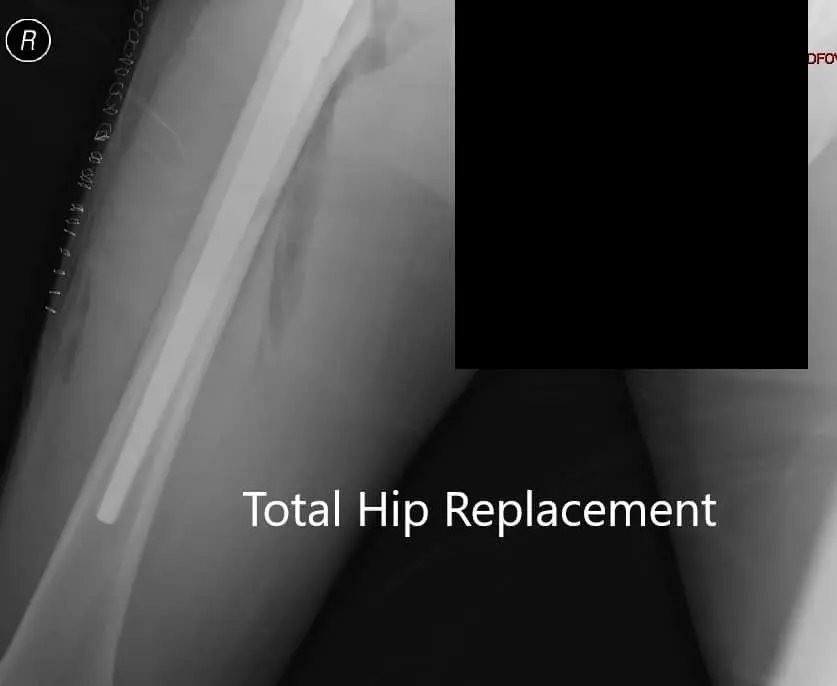

Postoperative X-ray showing AP view of the pelvis

Postoperative X-ray showing AP view of the pelvis - img 2

Postoperative X-ray showing AP view of the pelvis.